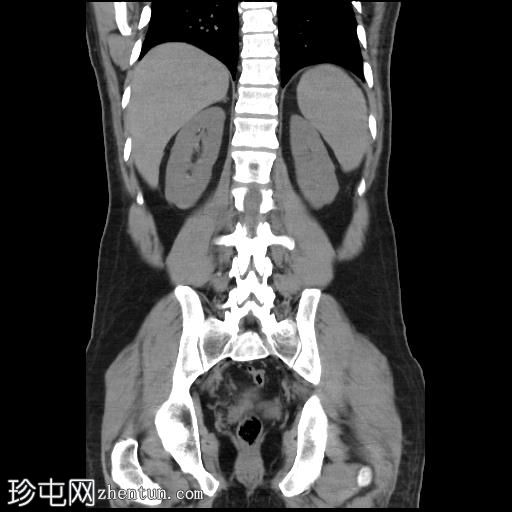

轴位增强扫描(门静脉期)

CT扫描显示胰腺组织完全包绕十二指肠第二段。未发现胰周结节或肿块。

左肝II段可见一强化病灶,提示快速充盈型血管瘤。

此外,肝实质内可见少量低密度病灶,但体积过小,无法准确定性。